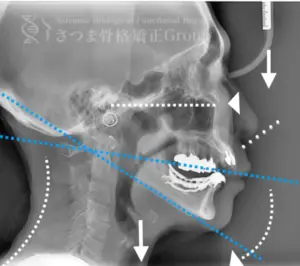

渋谷TMJ歯科クリニックでは、頭蓋および頸椎の歪みが顎位(あごの位置)と咬合(噛み合わせ)の乱れを引き起こし、その結果として顔の歪み、顎関節症、食いしばり、ストレートネックによる強い肩こり、さらには自律神経の乱れへとつながると考えています。

これらの問題を正確に評価するため、当院では セファロシステムによるレントゲン撮影(X-ray images) を行っています。

セファロ撮影によって 顎関節・頭蓋骨・頸椎の位置関係を客観的に可視化でき、施術前の状態を科学的に把握することが可能となります。

• 顎位のズレ

• 咬合の乱れ

• 頭位・頸椎姿勢のバランス

• 筋肉・関節の負担部位

施術の前後で撮影したレントゲン写真を比較することで、改善の度合いや変化を一目で確認できます。